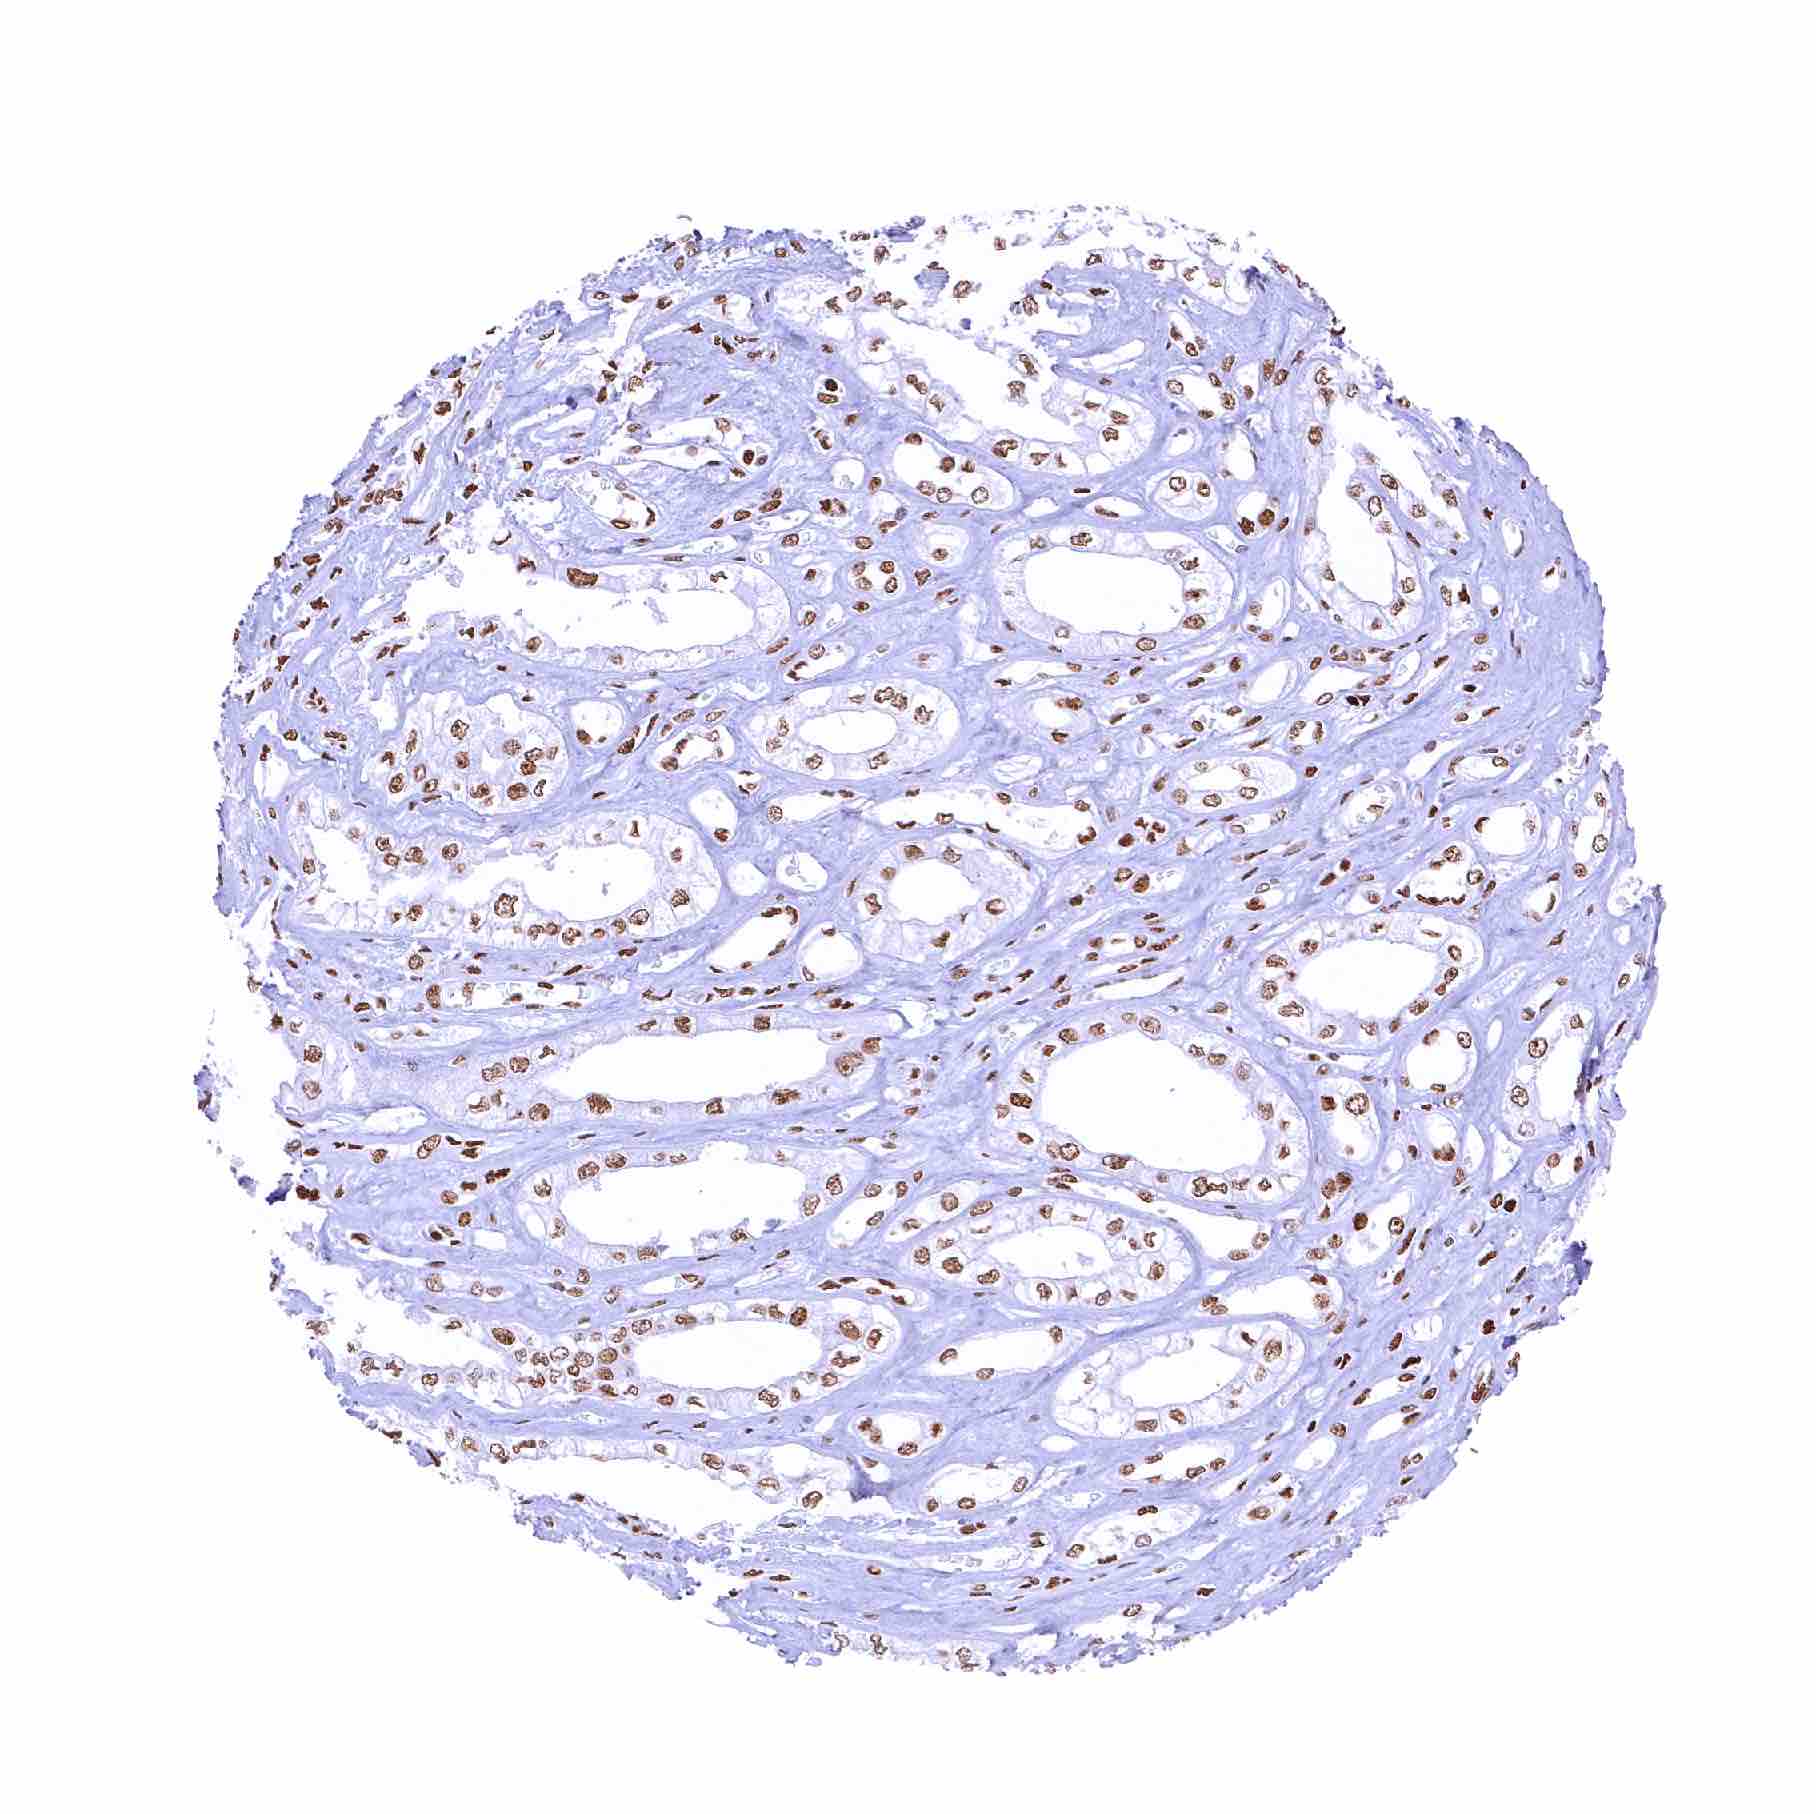

Kidney, cortex – Distinct PARP1 positivity of all cells.Staining is weakest in proximal tubuli

Kidney, cortex

Kidney, medulla